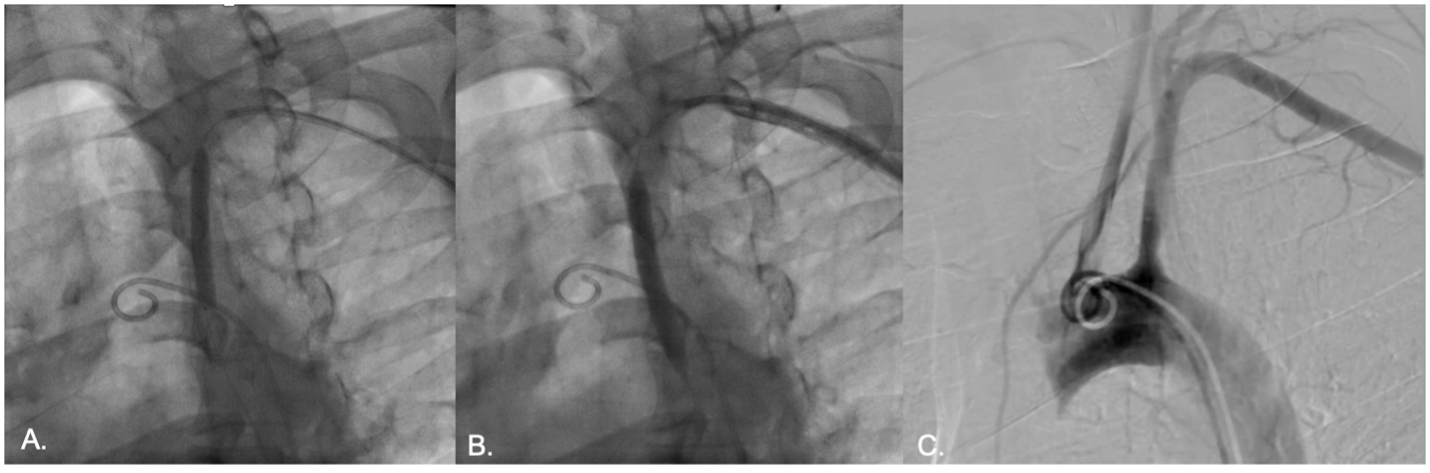

Vascular access was obtained via ultrasound-guided puncture of the left femoral and radial arteries. A 7 Fr radial GlideSheath and a 6 Fr femoral sheath were inserted. Double contrast injection using 5Fr pigtail in the aortic arch and JR 7Fr in the mid left subclavian atery, demonstrated total occlusion of the proximal left subclavian artery with retrograde flow in the left vertebral artery. The aortic pressure was 137/77 mmHg while the left subclavian artery was 104/66 mmHg.

The lesion was crossed using a 0.014-inch guidewire via a retrograde approach from the left subclavian artery. An intravascular ultrasound (IVUS) catheter was advanced, and IVUS evaluation revealed a fibrolipidic plaque with a dominant fibrotic component. The minimal lumen area (MLA) measured 4.01 mm©÷, and the lesion length was 28 mm. The distal vessel diameter ranged from 7.63 to 8.06 mm. Slow and gradual predilation was performed using a 4.0 x 60 mm non-compliant balloon at the proximal segment of the subclavian artery. Subsequent IVUS evaluation demonstrated an eccentric plaque with limited plaque dissection, without evidence of medial dissection or intramural hematoma (IMH). The post-dilation MLA was 22.35 mm©÷ with a diameter of 5.06–5.63 mm. A 7.0 x 60 mm drug-coated balloon (low-dose paclitaxel) was then inflated at the proximal subclavian artery for 180 seconds. Final angiographic evaluation showed minimal residual stenosis without evidence of vessel perforation or dissection. The left vertebral artery remained patent with antegrade flow. No significant pressure gradient was noted between the aorta and the left subclavian artery. At six-month angiographic follow-up, the left subclavian artery remained patent with good antegrade flow.